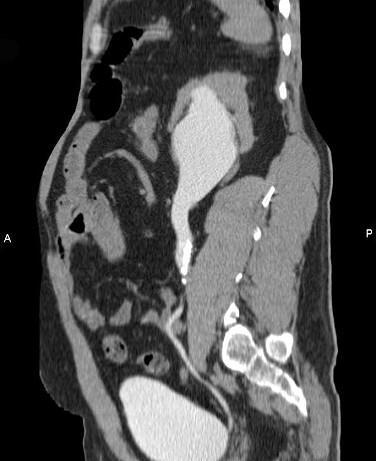

问题 男,42岁,反复左侧腰部疼痛伴血尿3个月余,CT检查如图,下列说法错误的是 ( )

选项 A、左输尿管结核并左肾积水 B、考虑为左输尿管结石并积水 C、左侧输尿管上段扩张 D、左侧肾盂肾盏扩张 E、左侧输尿管内可见多发的高密度影

答案 A